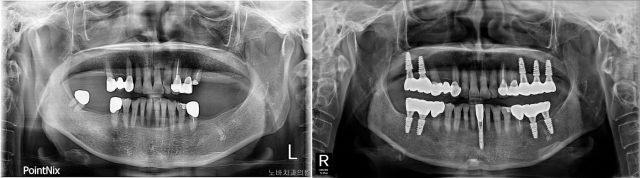

치아가 여러 개 빠진 뒤에도 치과 치료를 두려워해 위아래 부분 틀니를 착용하고 있던 61세 환자의 내비게이션 임플란트 수술 전(왼쪽)과 후 방사선 사진. 노바치과 제공 치아가 여러 개 빠진 뒤에도 치과 치료를 두려워해 위아래 부분 틀니를 착용하고 있던 61세 환자의 내비게이션 임플란트 수술 전(왼쪽)과 후 방사선 사진. 노바치과 제공

한 61세 여성 환자는 치과 치료에 대한 심한 공포증 때문에 다수의 치아를 잃고도 위아래 부분 틀니를 착용하고 있었다. 그러나 내비게이션 임플란트 수술 방식으로 다수의 임플란트 치료를 받고 난 뒤 불편한 틀니에서 해방될 수 있었다.